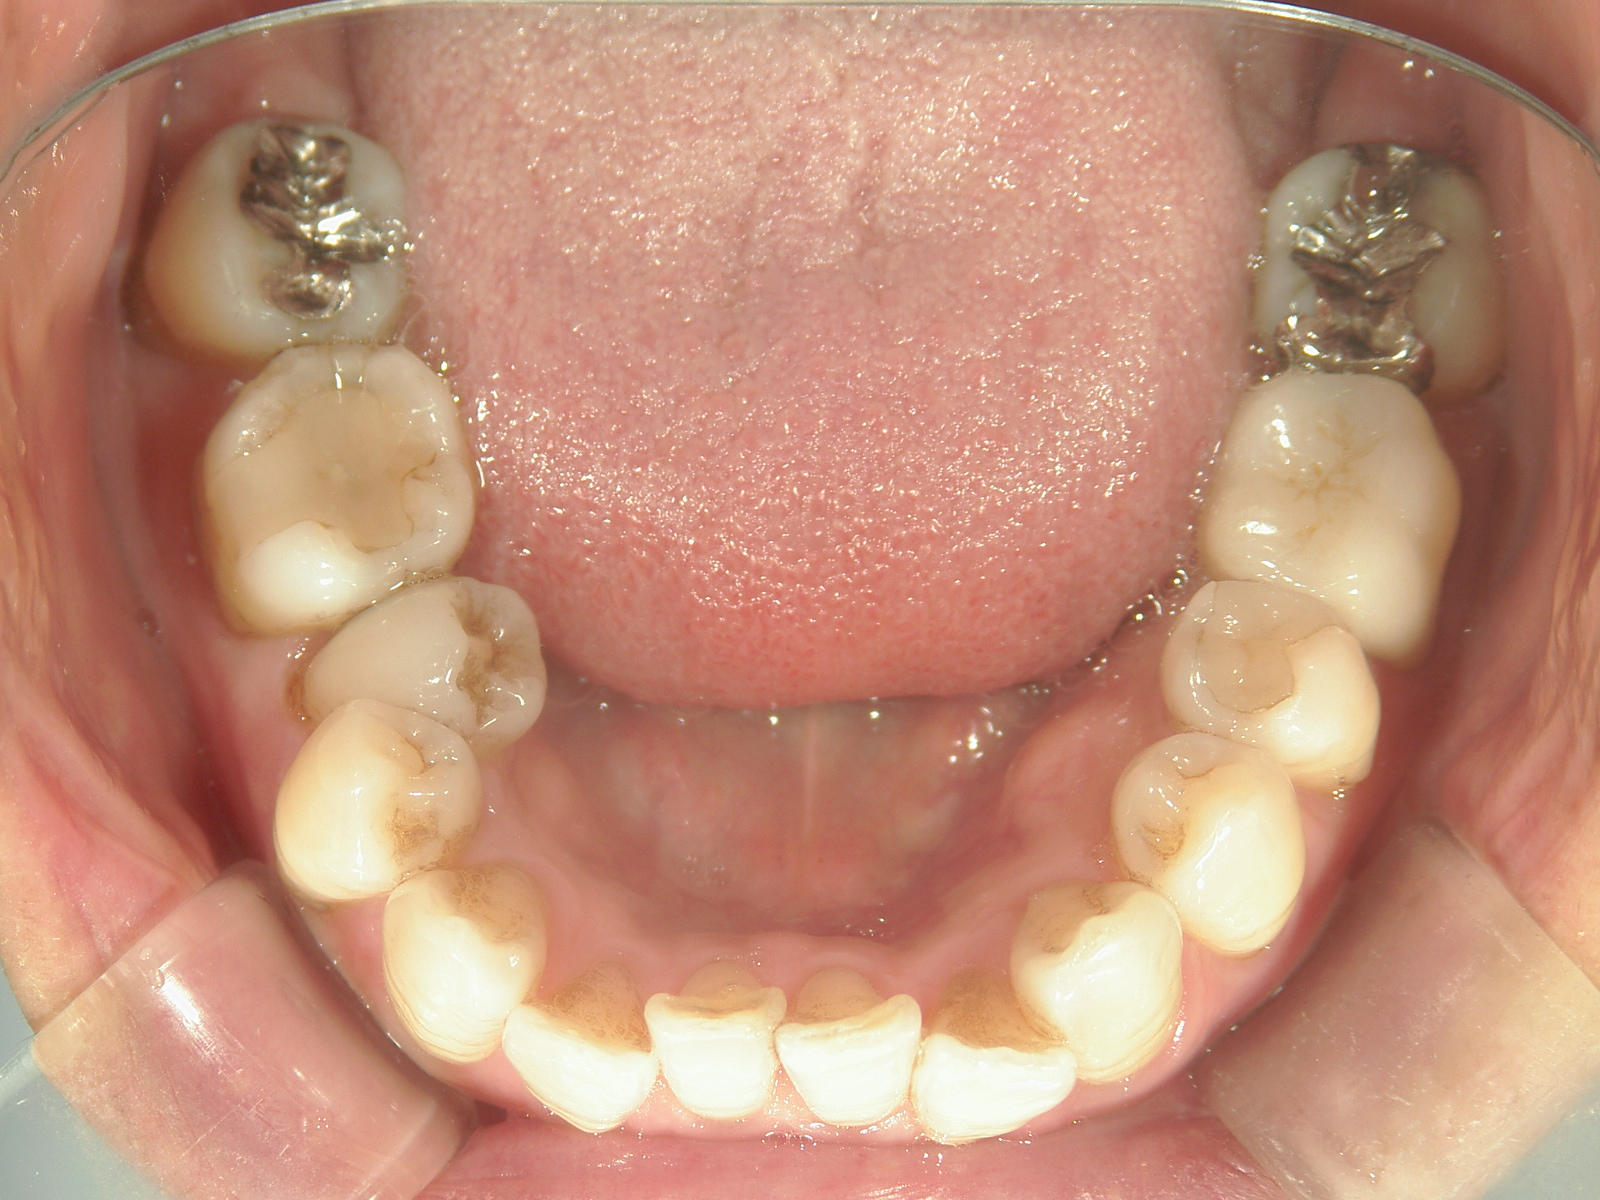

インビザライン矯正 症例(25)

主訴: ㊤前歯が出ていて、噛み合わせが気になる。

カテゴリー : ガタガタ(叢生)